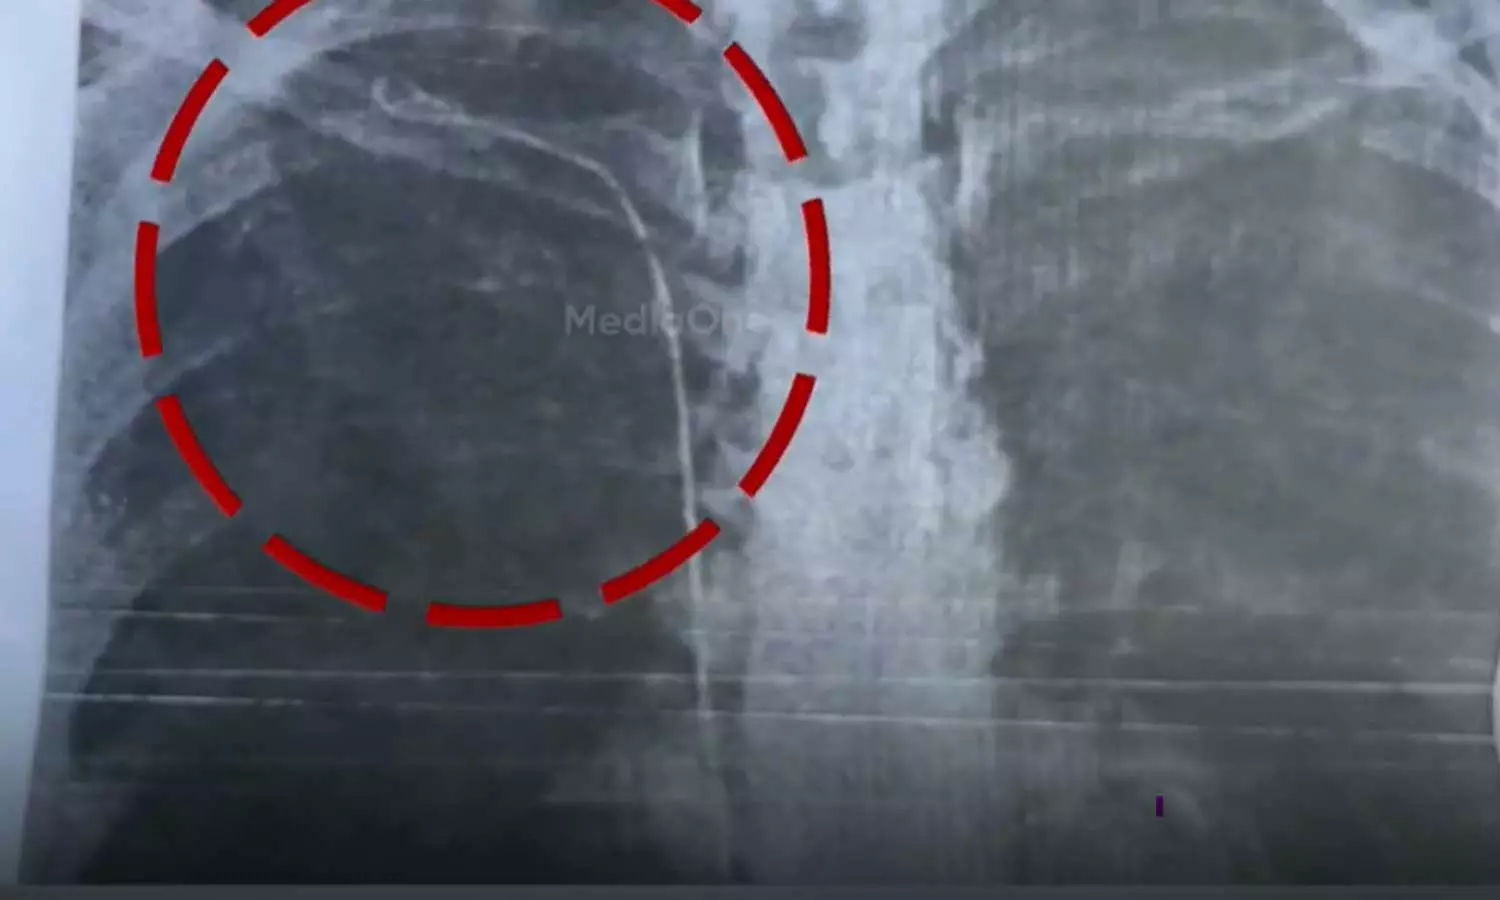

തൈറോയ്ഡ് ശസ്ത്രക്രിയക്ക് വിധേയയായ രോഗിയുടെ നെഞ്ചിലാണ് 50 സെന്റീമീറ്റര്‍ നീളം വരുന്ന ട്യൂബ് കുടുങ്ങിയത്

തൈറോയ്ഡ് ശസ്ത്രക്രിയക്ക് വിധേയയായ രോഗിയുടെ നെഞ്ചില്‍ 50 സെന്റീമീറ്റര്‍ നീളം വരുന്ന  ട്യൂബാണുള്ളത്. ശ്വാസംമുട്ടലിനെ തുടര്‍ന്ന് നടത്തിയ പരിശോധനയിലാണ് ട്യൂബ് കണ്ടെത്തിയത്. 2023 മാര്‍ച്ചില്‍ കാട്ടാക്കട മലയിന്‍കീഴ് സ്വദേശിനി സുമയ്യക്ക് നടത്തിയ ശസ്ത്രക്രിയയിലാണ് പിഴവെന്നാണ് ആരോപണം. ബന്ധുക്കള്‍ ഡിഎംഒയ്ക്ക് പരാതി നല്‍കി.

നിലവില്‍ ഡോക്ടര്‍ കയ്യൊഴിഞ്ഞ സ്ഥിതിയെന്ന് സുമയ്യ ആരോപിച്ചു. ട്യൂബ് നീക്കം ചെയ്യാന്‍ കഴിയാത്ത സാഹചര്യമെന്ന് മറ്റ് ഡോക്ടര്‍മാര്‍ രോഗിയുടെ ബന്ധുക്കളെ അറിയിച്ചു. നടക്കാന്‍ ബുദ്ധിമുട്ടും ശ്വാസംമുട്ടലും ഉണ്ടാകാറുണ്ടെന്നും എന്ന് രോഗി പറയുന്നു.